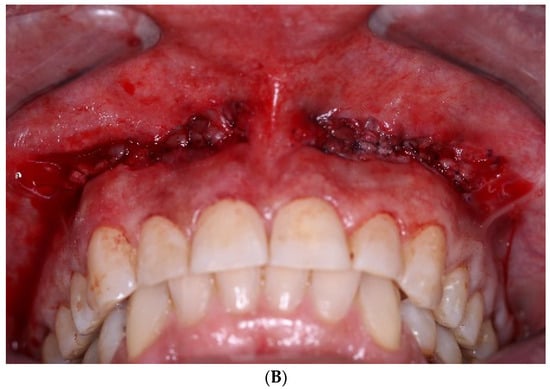

2. Case Presentation